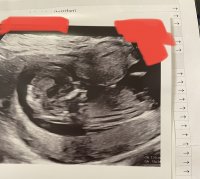

Ser man noe her? 12+2, målt til 12+6![]()

Hvis det er en nub jeg ser så tipper jeg jente<3

Nub teorien går ut på å gjette kjønnet ut i fra vinkelen "nuben" står i. Gutte-nub står mer opp og gjør det allerede fra uke 11-12. Jente-nub ligger mer flatt ned.

Så hvis noen har ultralydbilder fra uke 12 og utover de ønsker en tolkning på så legg gjerne inn her.Jeg har mange års erfaring med nub teorien og elsker å gjette kjønn